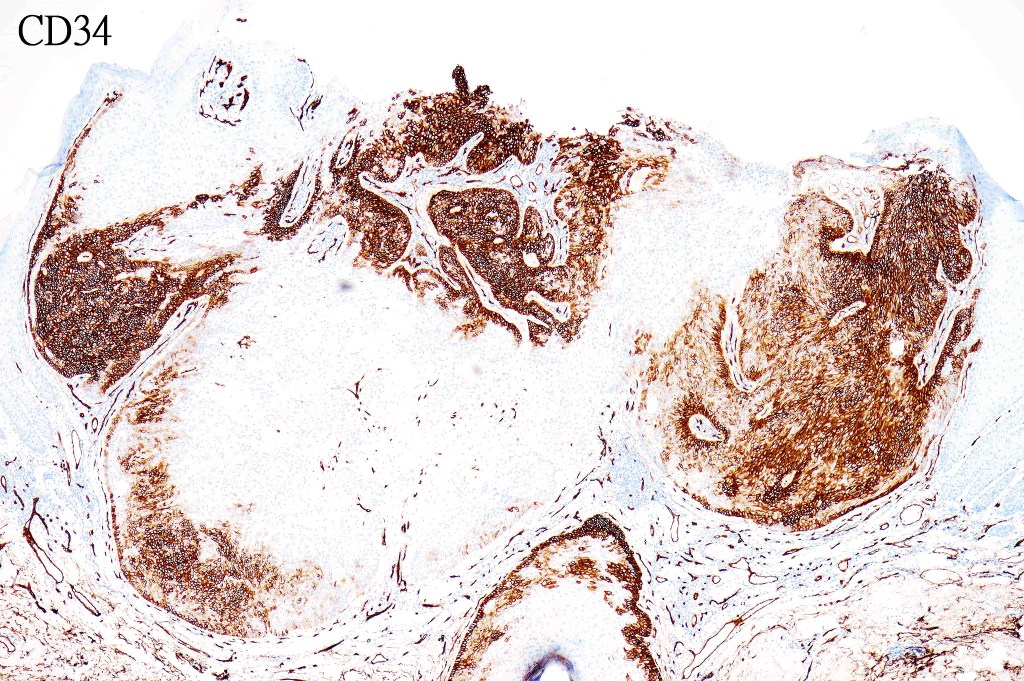

•CD34, p63 +ve

The diagnosis of both these tumors is nearly always readily apparent. The desmoplasia can result in suspicion of malignancy by the unwary. Trichilemmoma can be distinguished from poroma by the hyalinized thick basement membrane and absence of ducts. Desmoplastic trichilemmoma is distinguished from squamous carcinoma by the presence of typical trichilemmoma at the periphery and from trichilemmal carcinoma by the absence of pleomorphism & significant mitotic activity. Trichilemmal carcinoma does not show a pre-existent trichilemmoma. CD34 expression excludes squamous carcinoma